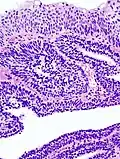

Histopathology representing an inverted papilloma of the urinary bladder that was cystoscopically resected. Hematoxylin and eosion stain. -

Inverted Schneiderian Papilloma of the Nasal Cavity. -

Inverted Schneiderian Papilloma of the Nasal Cavity with Abundant intraepithelial microabscesses.